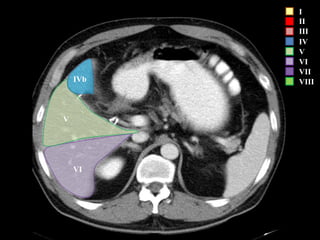

IVb III

I

II

III

IV

V

VI

VII

VIII

IVb

I – Entre cava y porta

II – el más superior de los izquierdos

III – Por debajo del II

IV – por delante de la vesícula

V – por detrás de la vesícula

VI – relación con riñón derecho

VII – el más posterior de los segmentos superiores

VIII – domo hepático

Las claves de la segm. Hepática